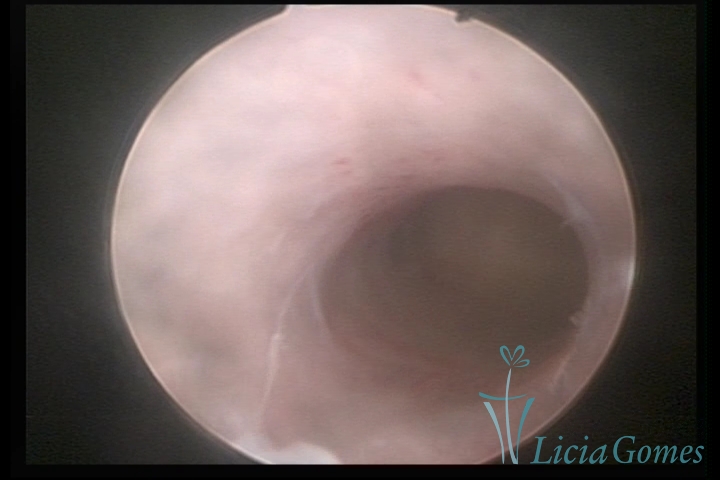

Third part or upper section

Presents the mucosa with a smooth, poorly vascularized surface, to the internal orifice